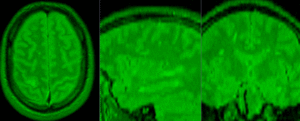

| − | |[[Image: | + | |[[Image:RegLib_C04_unregistered1.gif|300px]] ||baseline PD & contrast T1Gd before registration (click to enlarge) |

| − | |[[Image: | + | |[[Image:RegLib_C04_unregistered2.gif|300px]]||baseline and follow-up PD before registration (click to enlarge) |